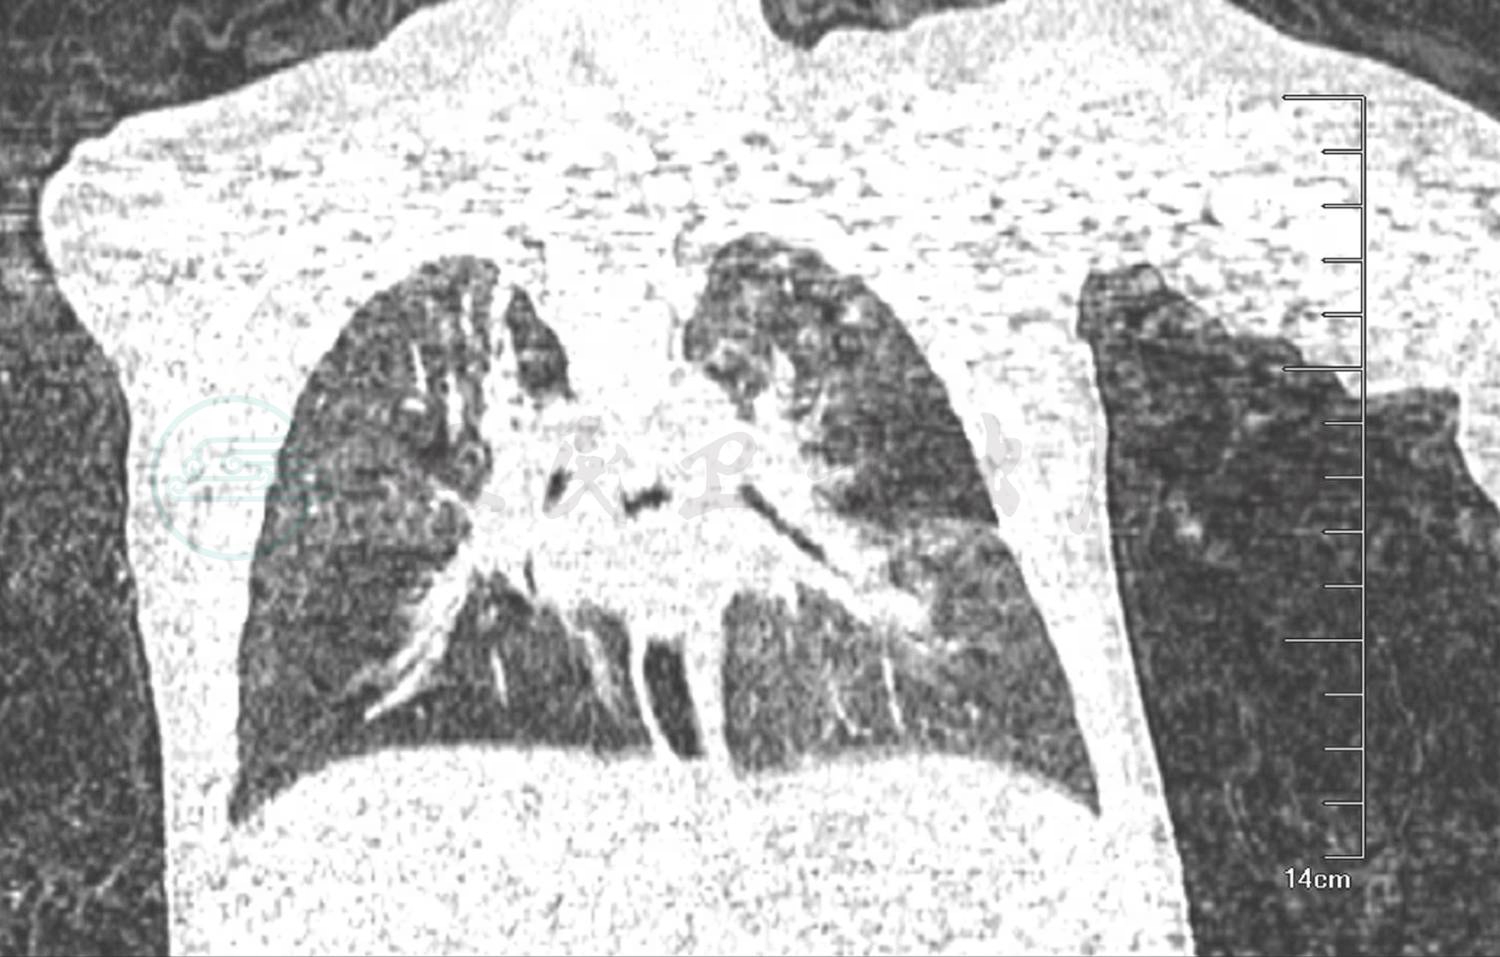

辅助检查:门诊血常规:WBC 10.7×109/L;NE% 37.0%;EO 1.41×109/L;Hb 119g/L;PLT 415 ×109/L。总IgE 5.3U/ml。食物-呼吸过敏原:牛奶、猫毛皮屑过敏。肺CT(图1、图2):双肺野透过度明显不均匀,小气道病变;多叶、段散在炎症,尤以右肺显著,伴右肺支气管显示不佳。

入院后予布地奈德及复方异丙托溴铵泵吸止喘,磺苄西林静脉滴注抗感染治疗。入院第2天化验结果回报:血气离子分析正常,尿、便常规正常,肝肾功能、心肌酶谱正常。CRP 1.46mg/L;结核抗体阴性;肺炎支原体抗体阳性(1:80);肺炎衣原体抗体-IgM阴性;肺炎支原体抗体-IgM阴性;肺炎支原体-DNA测定阴性(建议复查);病毒抗体八项未见明显异常。提示肺炎支原体感染不除外,予红霉素静脉滴注。免疫球蛋白:IGG 6.24g/L(正常4.81~12.21g/L),IGA 0.349g/L(正常 0.42~1.58g/L),IGM 1.38g/L(正常0.41~1.65g/L),IGA略低于正常下限。淋巴细胞亚群:总T细胞 73%(正常55%~84%),T抑制毒细胞44%(正常13%~41%),T辅助细胞23%(正常31%~60%),Th/Ts 0.52(0.71~2.78),NK细胞7%(正常7%~36%),总B细胞12%(正常5%~20%),暂不支持免疫缺陷。入院时肺CT(图1、图2):双肺野透过度明显不均匀,小气道病变,符合儿童哮喘的肺CT改变,但没有明显马赛克征改变,与闭塞性细支气管炎不相符,同时肺CT提示右肺支气管显示不佳,可能为管腔内阻塞:分泌物潴留?支气管异物?或是支气管管腔受压?因此,进一步纤维支气管镜检查成为我们关注的重点。入院第3天予完善纤维支气管镜检查:右主支气管黏膜光滑,略充血水肿,右肺下叶开口处可见黄白色异物(图3),用异物篮将异物取出,异物嵌顿处有大量肉芽组织增生(图4)。右肺上叶开口炎性狭窄明显,左肺各叶段支气管管腔开口通畅未见痰栓堵塞、狭窄及异物征象。异物取出后继续予雾化及抗感染治疗,患儿咳嗽及喘息较前明显缓解。住院治疗第6天,患儿偶有咳嗽,无喘息,肺部听诊无喘鸣音,好转出院。

图1 双肺透过度均匀,散在炎症,右肺支气管显示不清

图2 双肺透过度不均匀,散在炎症,右肺支气管显示不清